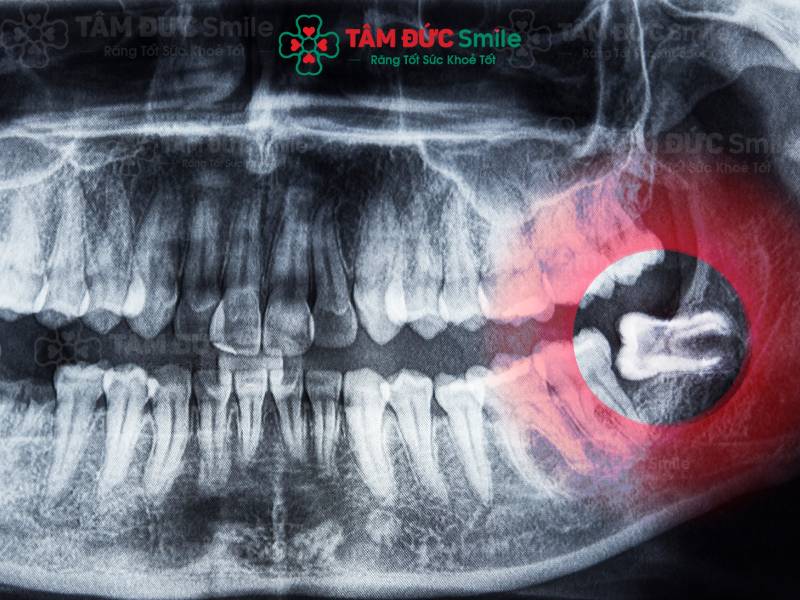

Trước khi nhổ răng khôn, bác sĩ tiến hành đánh giá hình dạng răng khôn bằng kết quả X-Quang. Từ đó, bác sĩ đưa ra phương án nhổ một cách an toàn và phù hợp nhất với từng mức độ răng.

Chụp X-Quang để đánh giá hình dạng và vị trí răng khôn